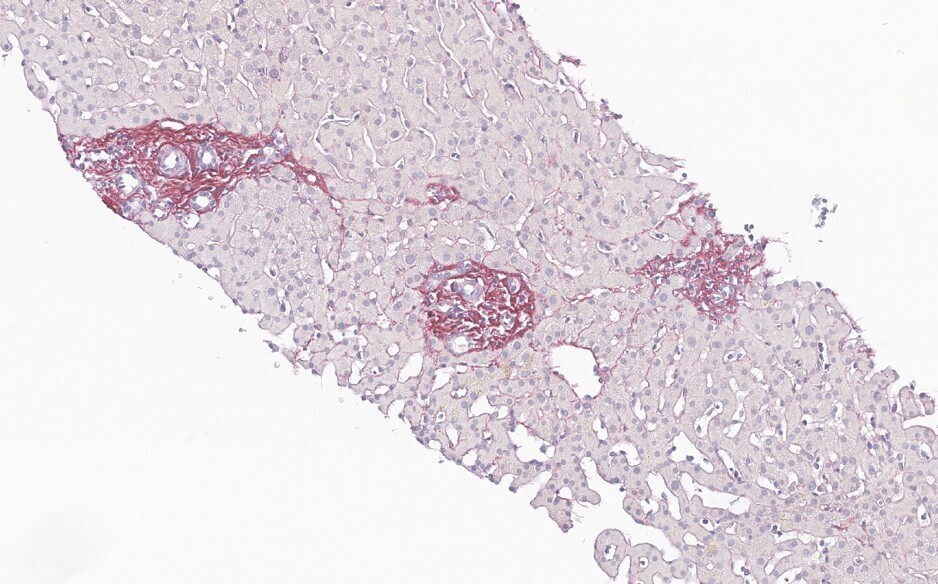

Dans un tiers des cas environ, la MVPS se révèle par une complication de l’hypertension portale (rupture de varices œsophagiennes et ascite, à parts égales).4 Le reste du temps, le diagnostic est posé lors d’explorations d’anomalies du bilan hépatique6 ou à la suite de la découverte fortuite de signes d’hypertension portale (splénomégalie, thrombopénie, varices œsophagiennes ou gastriques, voies de dérivation porto-systémiques en imagerie). Dans tous les cas, le diagnostic nécessite une biopsie hépatique, réalisée préférentiellement par voie transjugulaire (fig. 2 et 3).

La MVPS est en effet définie par l’absence de cirrhose attestée par une biopsie hépatique de bonne qualité, associée à au moins un signe histologique spécifique de MVPS, ou à au moins un signe spécifique d’hypertension portale, ou à au moins un signe histologique non spécifique de MVPS et à un signe non spécifique d’hypertension portale (tableau 2).7 Les signes d’hypertension portale ne sont donc pas systématiquement présents dans la MVPS.8